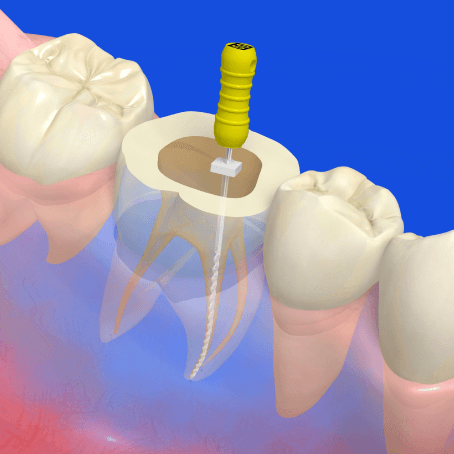

むし歯が進行した歯に対しては、通常歯髄(神経)を抜き、セメントなどの人工物を詰める治療(根管治療・人工物充填)が行われます。歯髄を抜いた歯に対して人工物を詰めるのではなく、神経をよみがえらせて抜歯のリスクを減らす治療法が歯髄再生療法です。

歯髄再生療法は、抜歯した不要歯から培養した歯髄幹細胞を歯の根管内へ移植することで歯髄(自分の神経)が再生するという治療です。歯の寿命も延び、むし歯の予防やご自身の歯で食事を存分に楽しめるなど、さまざまな健康効果が期待できます。

1. 1

治療対象となる歯の

神経を抜いて清掃

2. 2

培養した歯髄幹細胞と

薬剤を移植する

3. 3

神経が再生し

「健康な歯」を取り戻します。